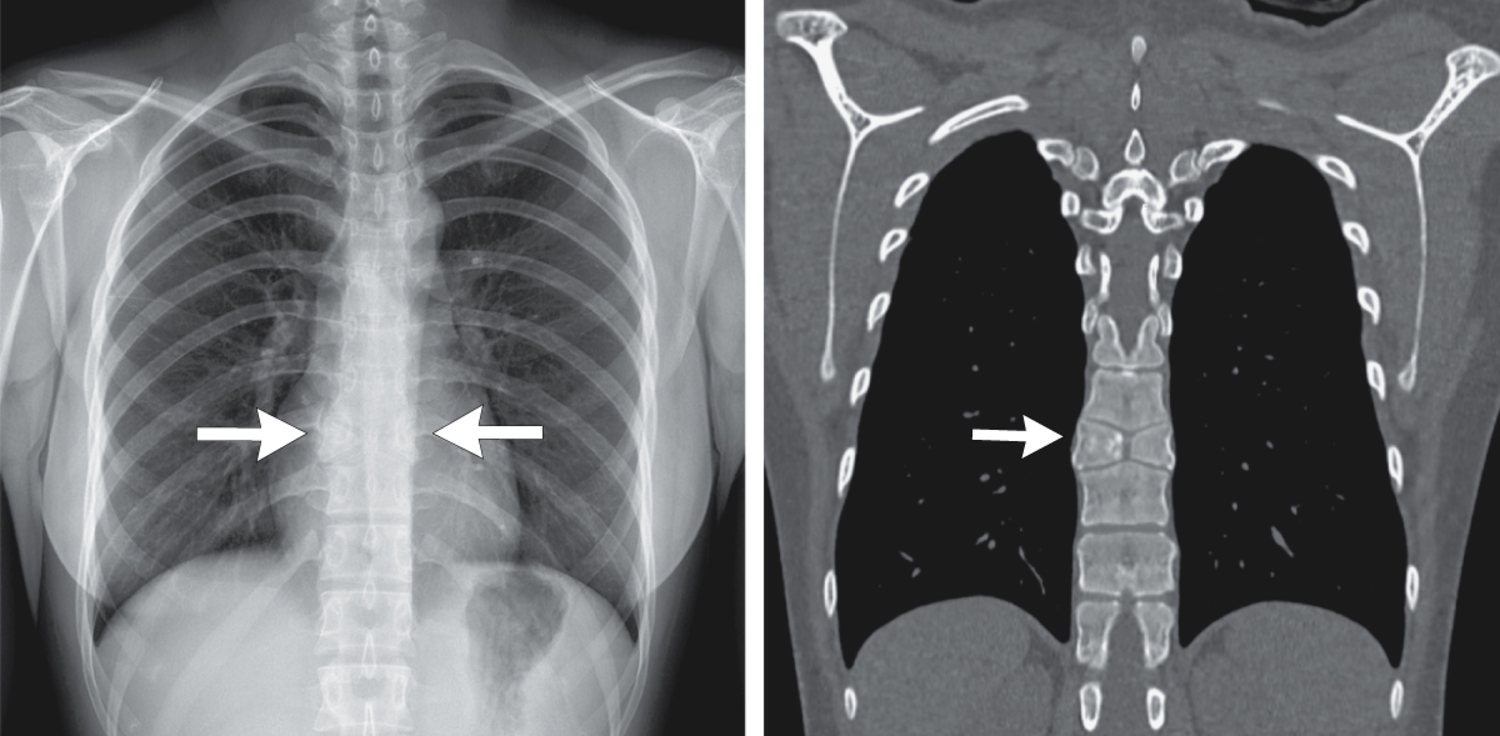

A 21-year-old woman who had presented to the pulmonary clinic with a 7-day history of sore throat and cough was noted to have a vertebral abnormality on chest radiograph. She reported no history of back pain. Computed tomography of the chest is shown. What is the most likely underlying etiology?

诊断为蝴蝶椎。蝴蝶椎是一种罕见的先天性畸形,是由于胚胎发育过程中两侧椎体骨化中心未能融合所致。它通常无症状,是在影像学检查中偶然发现的。蝴蝶椎可能单独存在,也可能与其他先天性畸形相关。医生向患者解释了这一脊椎异常的良性本质,给予了相应的安抚。